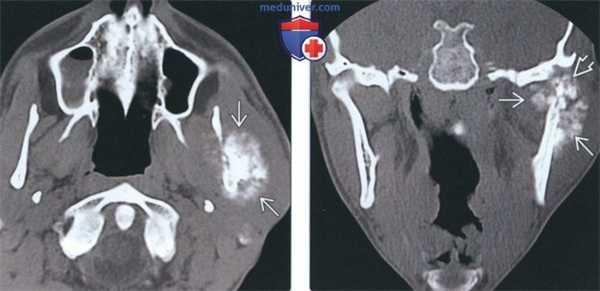

(Слева) На аксиальной КТ в костном окне визуализируется большая агрессивная остеосаркома со стороны наружного края ветви нижней челюсти. Определяется лучистая периостальная реакция, виден остеоидный матрикс.

(Справа) На корональной КТ в костном окне у этого же пациента определяется лучистая периостальная реакция со стороны внутреннего и наружного края ветви с «пятнистой» деструкцией и увеличением мыщелка.